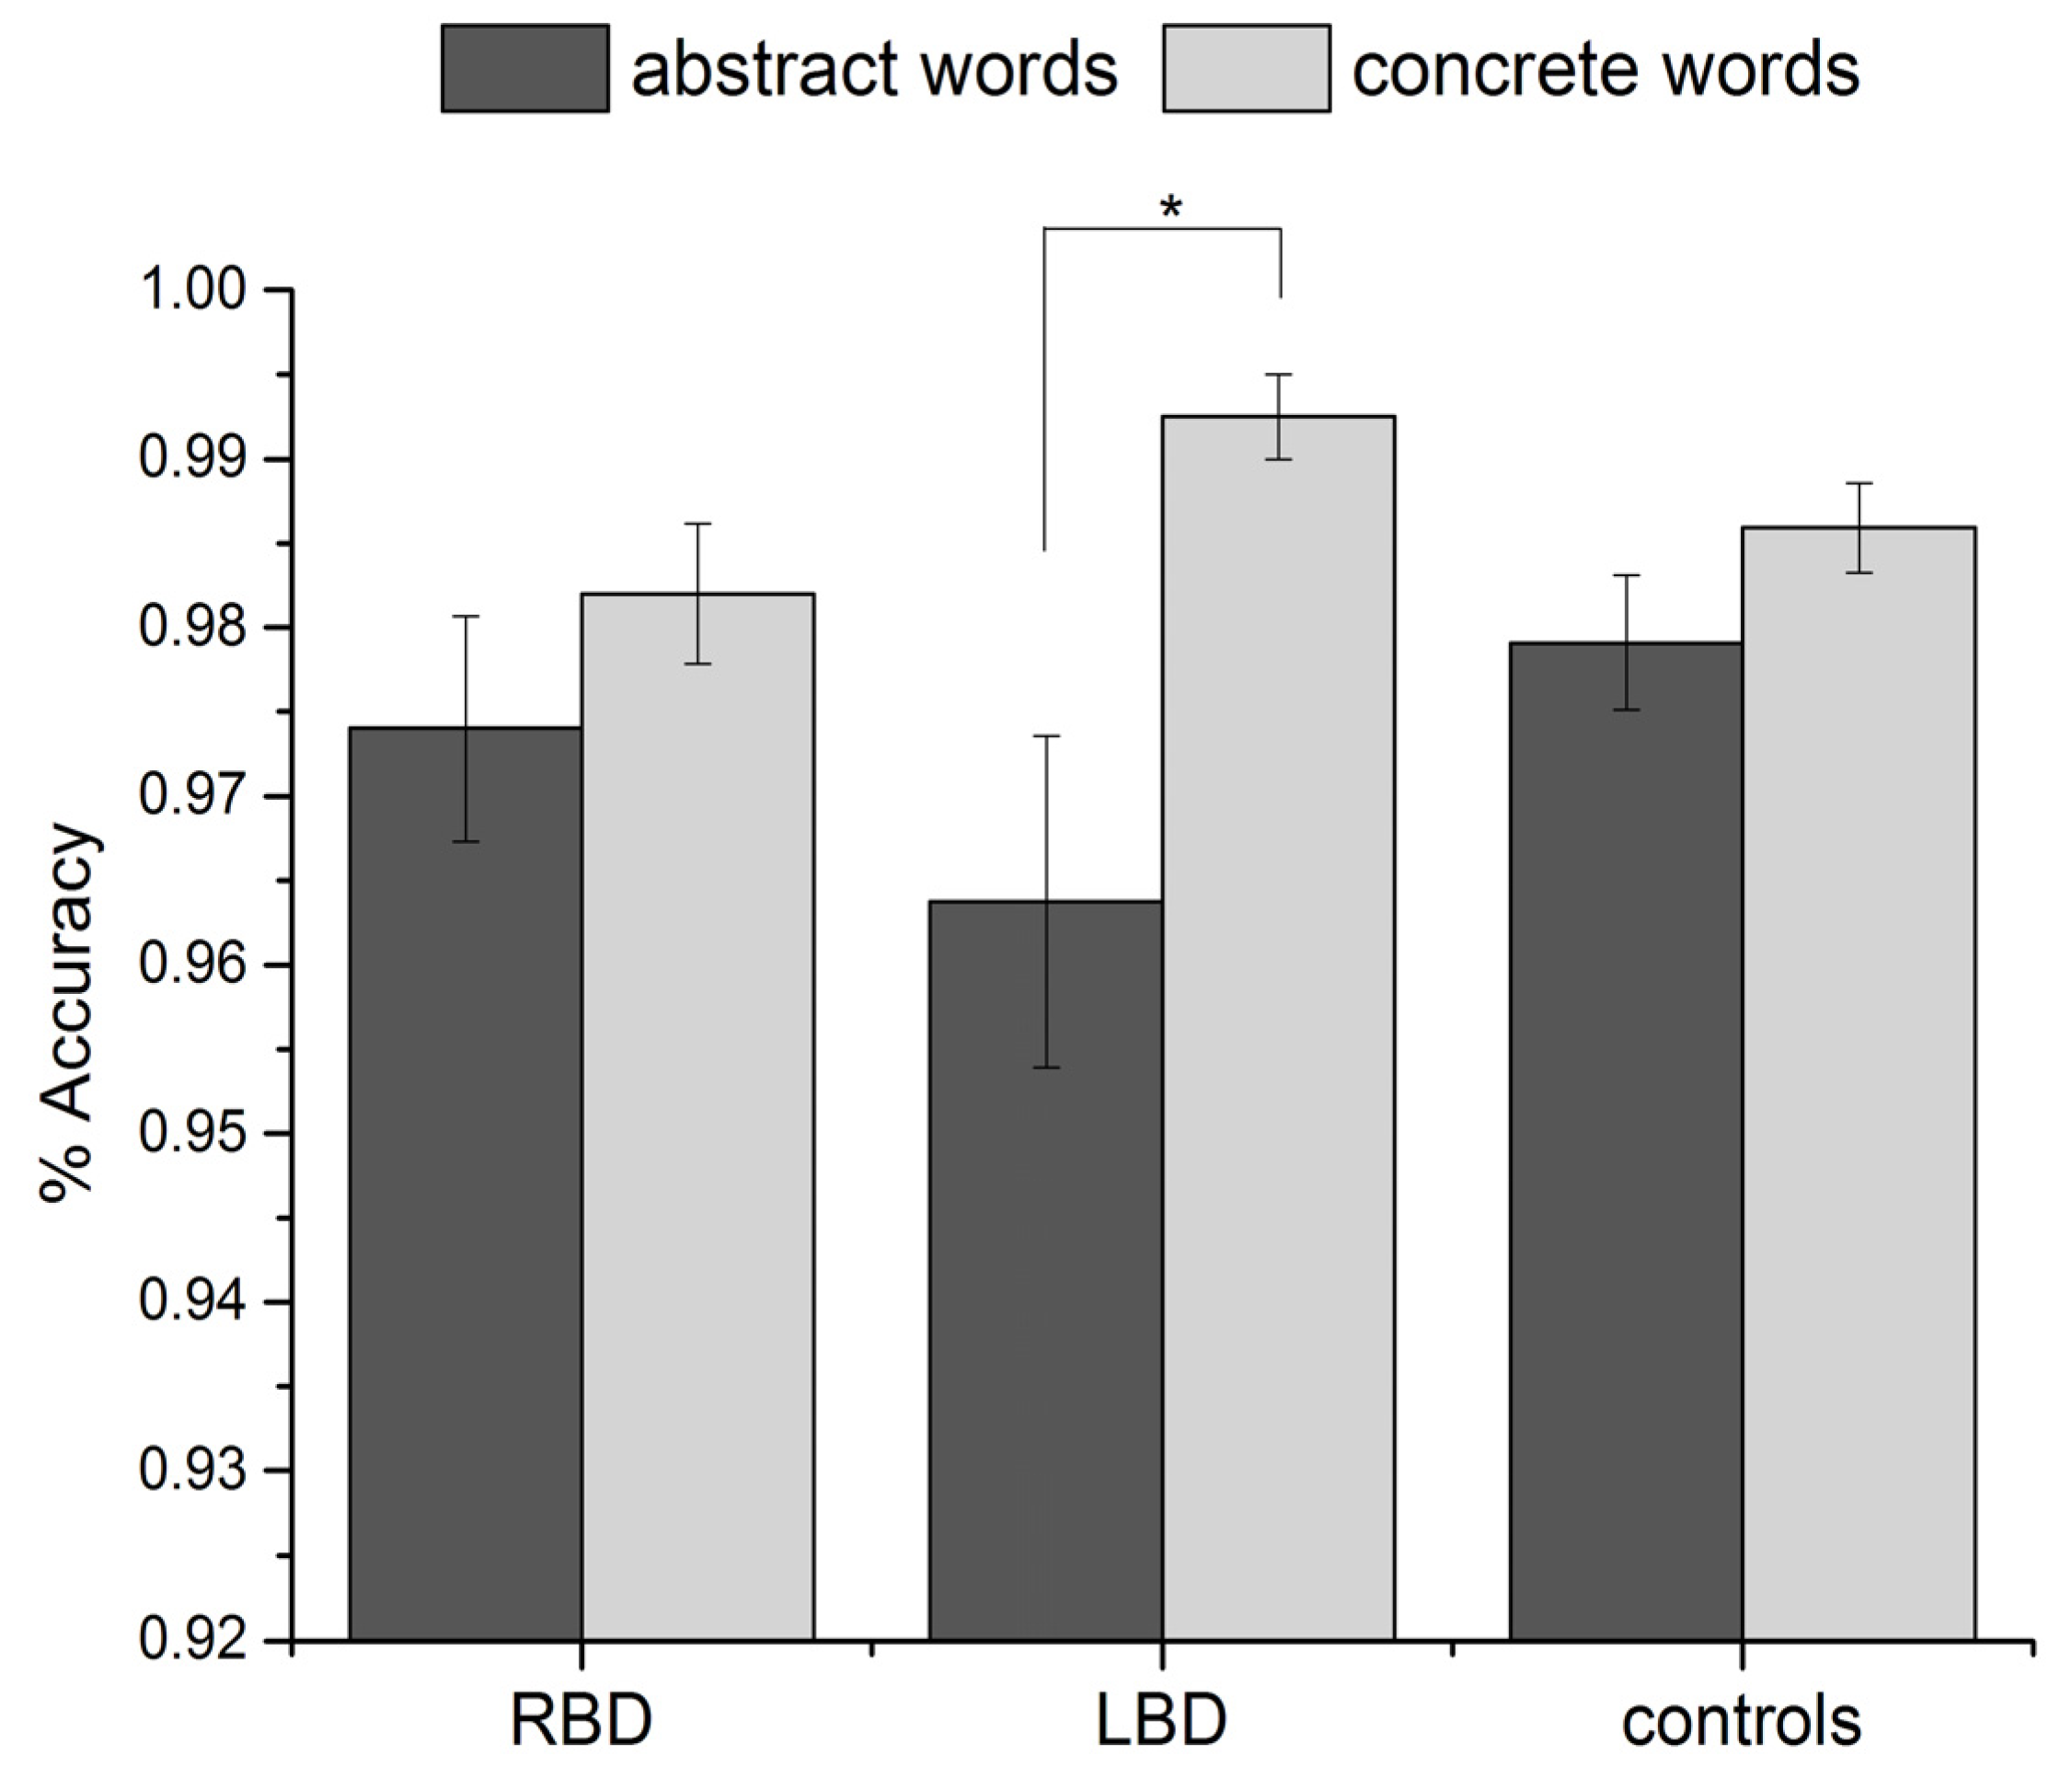

Regarding accuracy (see

Figure 1), the main effect of word type was significant [

F(1, 37) = 16.5,

p = 0.001, partial eta square = 0.31], with a lower number of correct responses for abstract than concrete words; the effect of group was not significant [

F(2, 37) = 0.5,

p = 0.6]. The interaction group × word type was significant [

F(2, 37) = 3.5,

p = 0.04, partial eta square = 0.16].

Post-hoc analyses (Tukey test) showed that left temporal patients produced significantly more errors with abstract than concrete words (

p = 0.004). This difference was not significant in RBD patients (

p = 0.8) or in controls (

p = 0.6) (see

Figure 1).

Figure 1.

Percentage of correct responses for abstract and concrete words in RBD, temporal LBD and controls. Error bars represent standard errors of the mean.

Figure 1.

Percentage of correct responses for abstract and concrete words in RBD, temporal LBD and controls. Error bars represent standard errors of the mean.